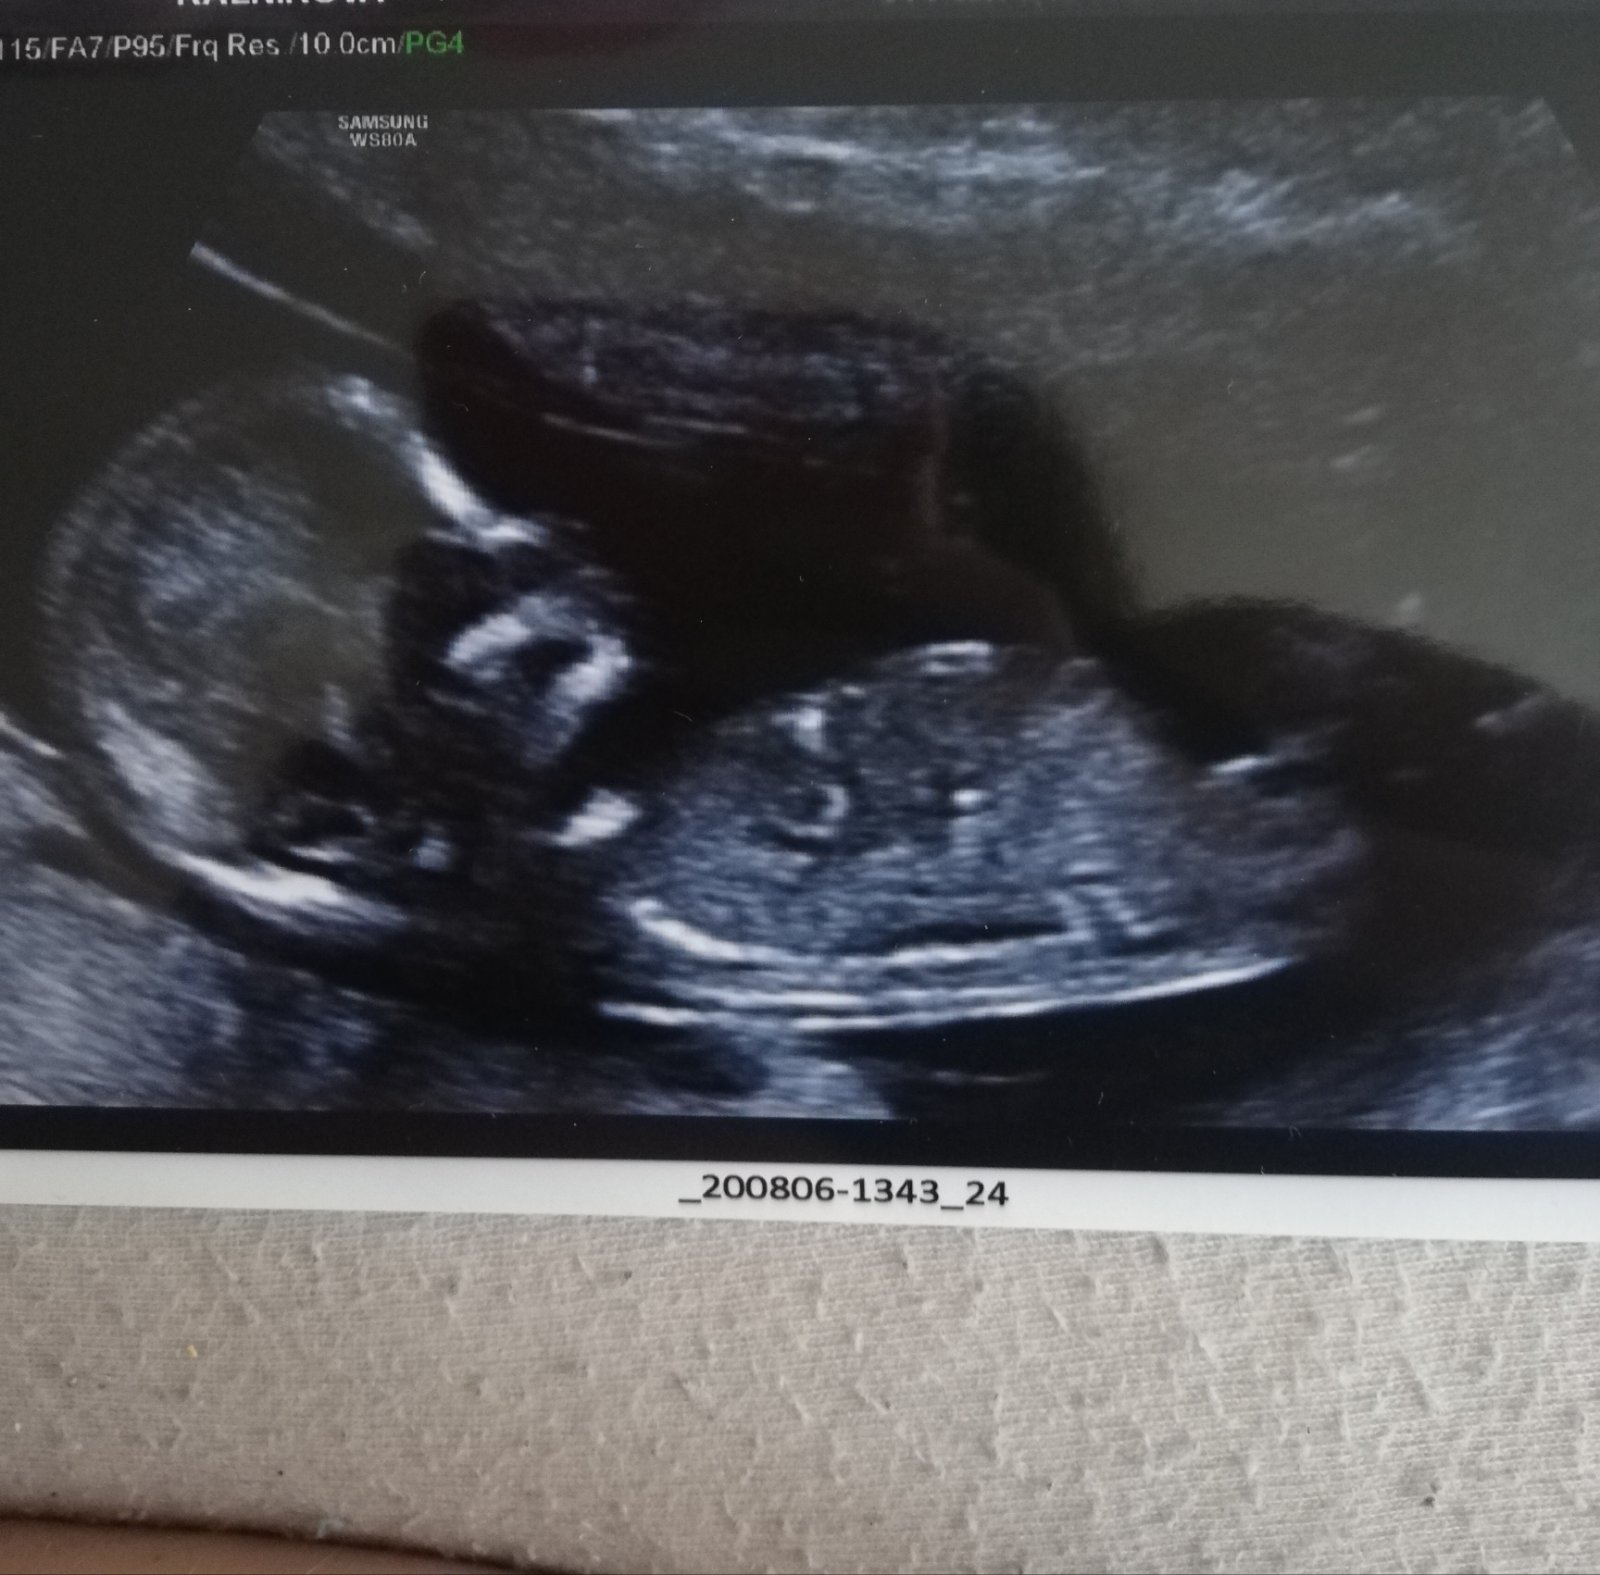

Je to holčička nebo chlapeček? Foto ultrazvuku

Mám další fotku do diskuze ☝️😃

@allisenka 100% 🙂 pohlavní hrbolek je hezky rovně. Na té minule fotce to jde vidět úplně krásně. Mám dvě holky a úplně stejné. Chlapečci mají hrbolek jakoby nahoru, jako by trčel 🙂

@rennye podle utz 12+6 podle menzesu 12+4.

@rennye anooo, pan doktor řekl také chlapečka ☺️❤️

@rennye ale mátl mě pořád ten sklon toho hrbolku 🤣 nepřišel mi ani úplně nahoru a ani úplně rovně 🤣 tak jsem si furt říkala, zda se nemohl pan doktor splést, ale myslím si, že se to už moc nestává 🤣🤣🤣

@almidrob2539 To není noha, to co já myslím, ale pupečník určitě. A pindík to není. Vypadá to fakt na holku i podle té další fotky 😉